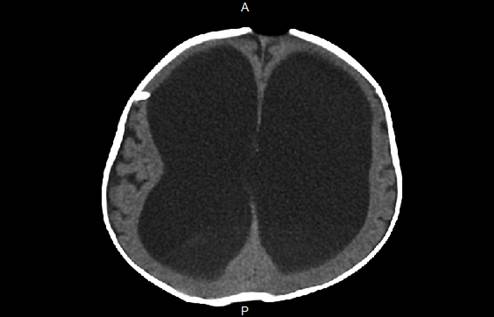

Se inició el manejo con antibiótico con ceftriaxona (100 mg/kg/día) y vancomicina (15 mg/kg cada 6 horas) por LCR compatible con la infección. La tomografía cerebral computarizada (TAC) (Figura 1), tomada en el día 1 de la estancia hospitalaria, evidenció una ventriculomegalia supratentorial e infratentorial, sin signos de paso transependimario de LCR sugestivo de hidrocefalia. Se realizó el retiro de la DVP con hallazgos intraoperatorios de la válvula programable de Hakim con detritos y secreción seropurulenta en su interior y se procedió a la colocación de la ventriculostomía externa, sin complicaciones.